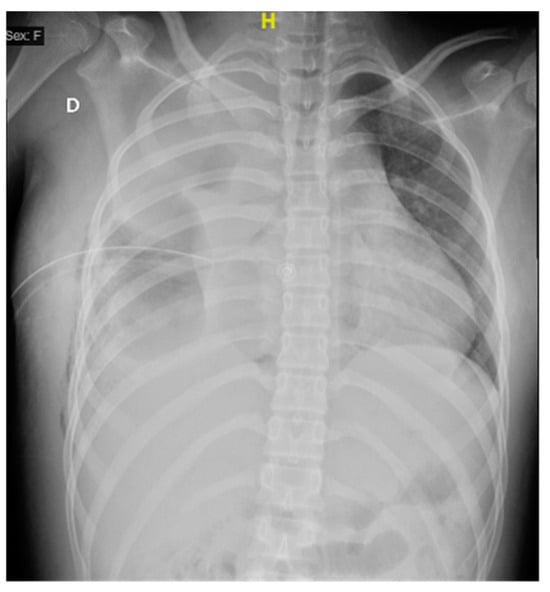

Upon admission to the emergency department of our hospital, she scored 15 on the Glasgow scale, requiring oxygen support with a face mask at 10 L/min, presented polypnea, the right hemithorax amplexation was decreased, and oxygen saturation of 89%. In addition, the right pleural tube showed 370 mL of hematopurulent output with a total of 128 mL (2.9 mL/kg/h) in 24 h. The gasometric study at the intake showed acid–base balance, hypoxemia, and normolactatemia (Figure 1).

Figure 1. Anteroposterior thoracic X-ray taken on admission shows a right pleural tube and right pleural effusion with loss of the costophrenic angle and radiopacity in the right lung.